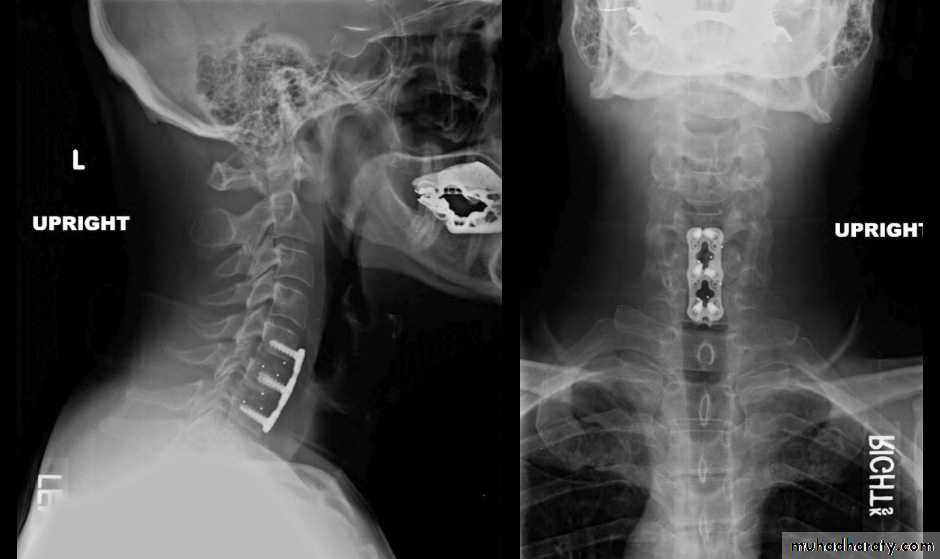

Laminotomy and micro-discectomy.Laminotomy: Ligamentum flavum on the relevant side and at the relevant level is removed, if necessary with some margin of the bordering laminae and medial third of the facet joint. The dura and nerve root are then gently retracted towards the midline and disc is excised.

Micro-discectomy is essentially similar to the standard posterior operation, except that the exposure is very limited and the procedure is carried out with the aid of an operating microscope.